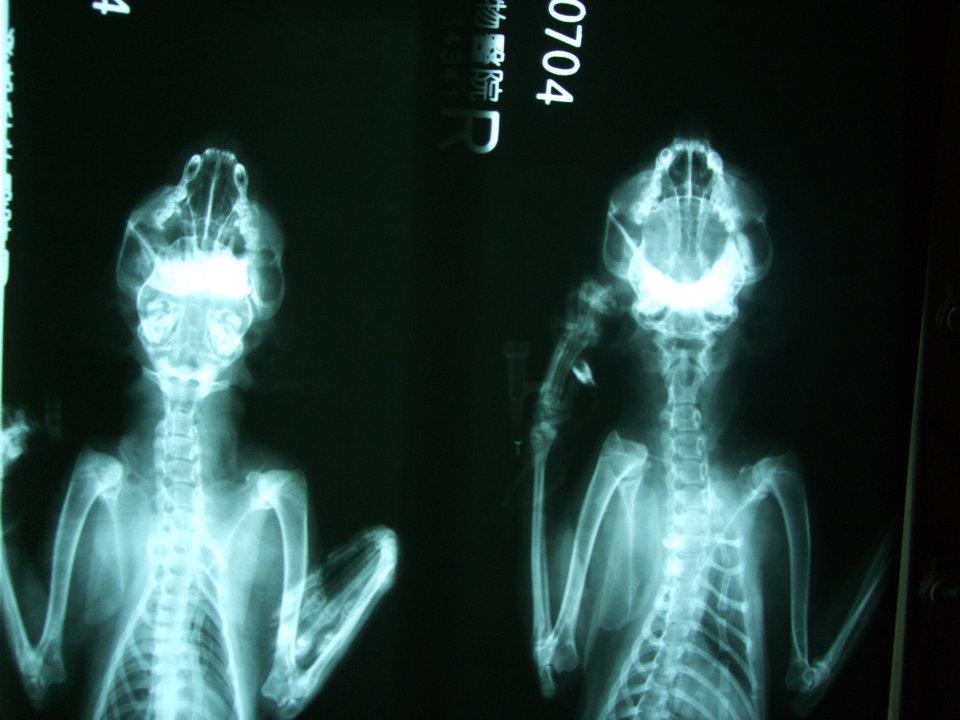

主題: 下顎、腿多處骨折的蜘蛛人 申請者姓名: 岳丹楓 花色: 申請日期: 2012-07-15 12:45:03 申請者部落格: 申請者臉書網址: 所在縣市/合作醫院: 台北市/澄毅動物醫院 治療費用: 4800元 需求人數: 12人 已結案 (2013-06-27 13:22:09) 報名人員: Bei Bei Wang(已付款)、Bei Bei Wang(已付款)、陳比比(已付款)、Ru Shiuan Liu(已付款)、SY Liou(已付款)、SY Liou(已付款)、牡羊先生(已付款)、Pomelo Peng(已付款)、Pomelo Peng(已付款)、orange liu(已付款)、Ku-ai Gina Chen(已付款)、艾薇拉、Kent、Athena Athena Tzeng、sally(已付款)、 候補人員: Patty Chen、julie lee、小P、 動物病情說明: 岳姊通報:陳小姐在龍門里捕捉or拾獲貓咪,嘴巴無法閉合行走姿勢怪異,送至醫院X光檢查發現腿部多處骨折、下顎骨折無法進食,插鼻胃管灌食,上點滴維持體力。